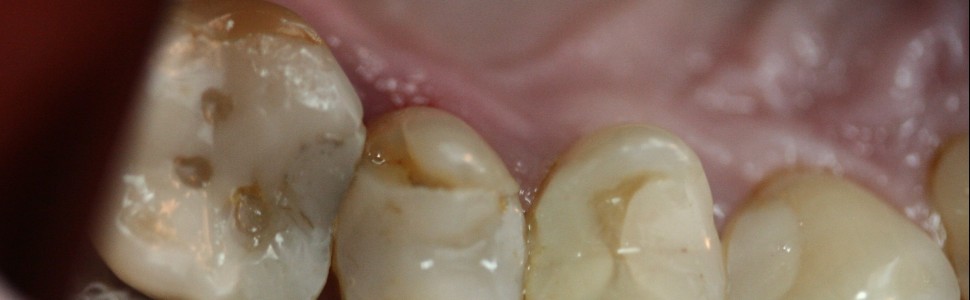

Pionowe złamanie korzenia drugiego zęba przedtrzonowego szczęki – wieloetapowe postępowanie terapeutyczne od ekstrakcji do estetycznego uzupełnienia braku

Vertical root fracture in second maxillary premolar – multi‑stage therapy from extraction to aesthetic reconstruction

W artykule przedstawiono kompleksowe leczenie zaplanowane po zdiagnozowaniu pionowego złamania korzenia drugiego zęba przedtrzonowego górnego. W wyniku wieloetapowej terapii obejmującej: atraumatyczną ekstrakcję, procedurę zachowania wyrostka z uszczelnieniem zębodołu i odbudowę protetyczną w postaci kombinowanego mostu z przęsłem owalnym, uzyskano zadowalający efekt funkcjonalny i estetyczny.

The article presents comprehensive treatment planned after the diagnosis of a second upper premolar vertical root fracture. As a result of the multi‑stage therapy which included atraumatic extraction, alveolar ridge preservation with socket seal surgery and prosthetic reconstruction in the form of a combined bridge with an ovate pontic, a satisfactory functional and aesthetic effect was obtained.